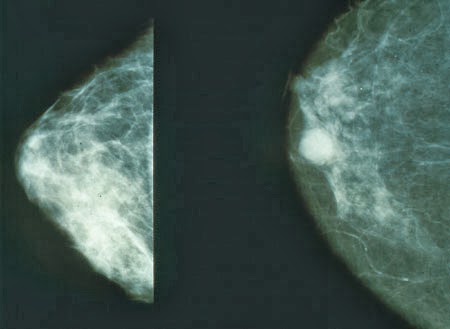

Immagine di una

mammella sana (sinistra)

e una con un tumore (destra)